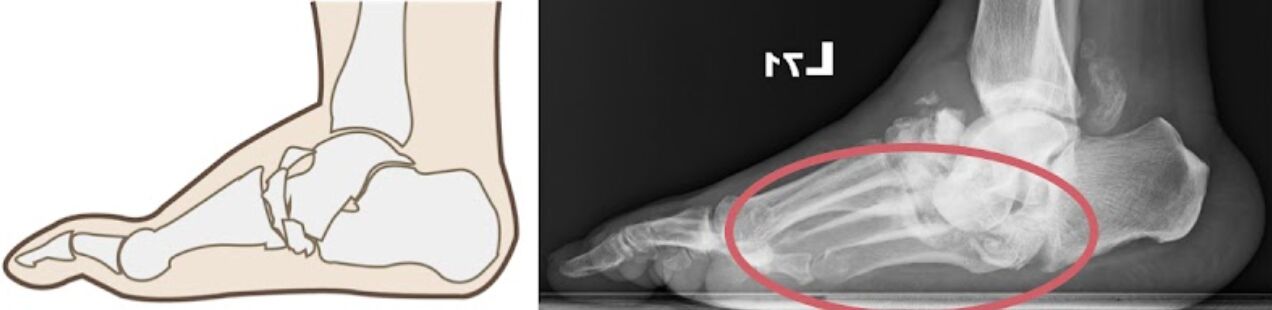

典型:夏柯氏足(Charcot foot)

->夏柯氏神經骨關節病變(Charcot neuro-osteoarthropathy)

->病變:足弓喪失、中足破壞

->足弓中斷:阿基里斯腱接在踝關節周圍→中足關節(附蹠關節)中斷塌陷=Tarsometatarsal joint(Lisfranc joint)

夏柯氏足 (Charcot foot) 是糖尿病足的一種並發症,通常與周圍神經病變有關,導致足部和踝關節的骨骼及軟組織變形。其特徵是骨骼和關節的突發性破壞,並且會導致關節變形及腫脹。常見的表現包括足部和踝部的 不穩定和變形,可以進一步引起關節中斷變形。